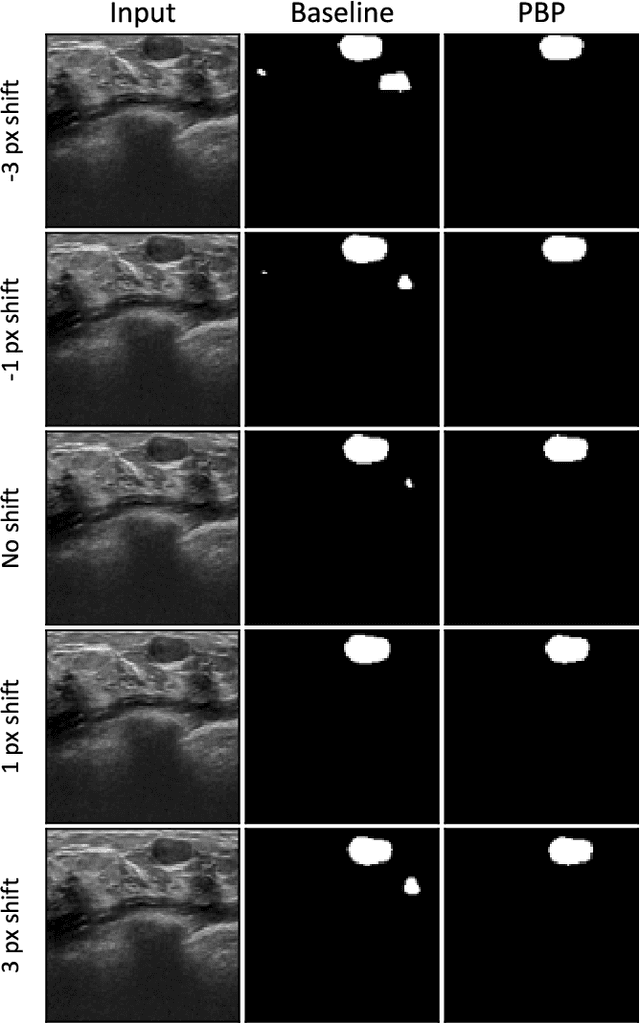

Abstract:While accuracy is an evident criterion for ultrasound image segmentation, output consistency across different tests is equally crucial for tracking changes in regions of interest in applications such as monitoring the patients' response to treatment, measuring the progression or regression of the disease, reaching a diagnosis, or treatment planning. Convolutional neural networks (CNNs) have attracted rapidly growing interest in automatic ultrasound image segmentation recently. However, CNNs are not shift-equivariant, meaning that if the input translates, e.g., in the lateral direction by one pixel, the output segmentation may drastically change. To the best of our knowledge, this problem has not been studied in ultrasound image segmentation or even more broadly in ultrasound images. Herein, we investigate and quantify the shift-variance problem of CNNs in this application and further evaluate the performance of a recently published technique, called BlurPooling, for addressing the problem. In addition, we propose the Pyramidal BlurPooling method that outperforms BlurPooling in both output consistency and segmentation accuracy. Finally, we demonstrate that data augmentation is not a replacement for the proposed method. Source code is available at https://git.io/pbpunet and http://code.sonography.ai.